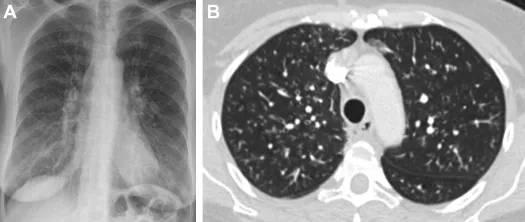

Риновірус в легенях. Фото ілюстративне: Science Direct

Важливо! Вірус виявили у легенях жінки, яка померла у 1770-х роках. Зразок зберігався у фондах Хантеріанського музею в Глазго.

Порівняння з базами показало, що знайдений вірус належить до групи риновірусів A, але представляє зниклу еволюційну гілку, споріднену із сучасними генотипами.

Ймовірно, їхній спільний предок існував ще у 17 столітті. У тканині також виявили бактеріальні патогени, зокрема збудників пневмонії.